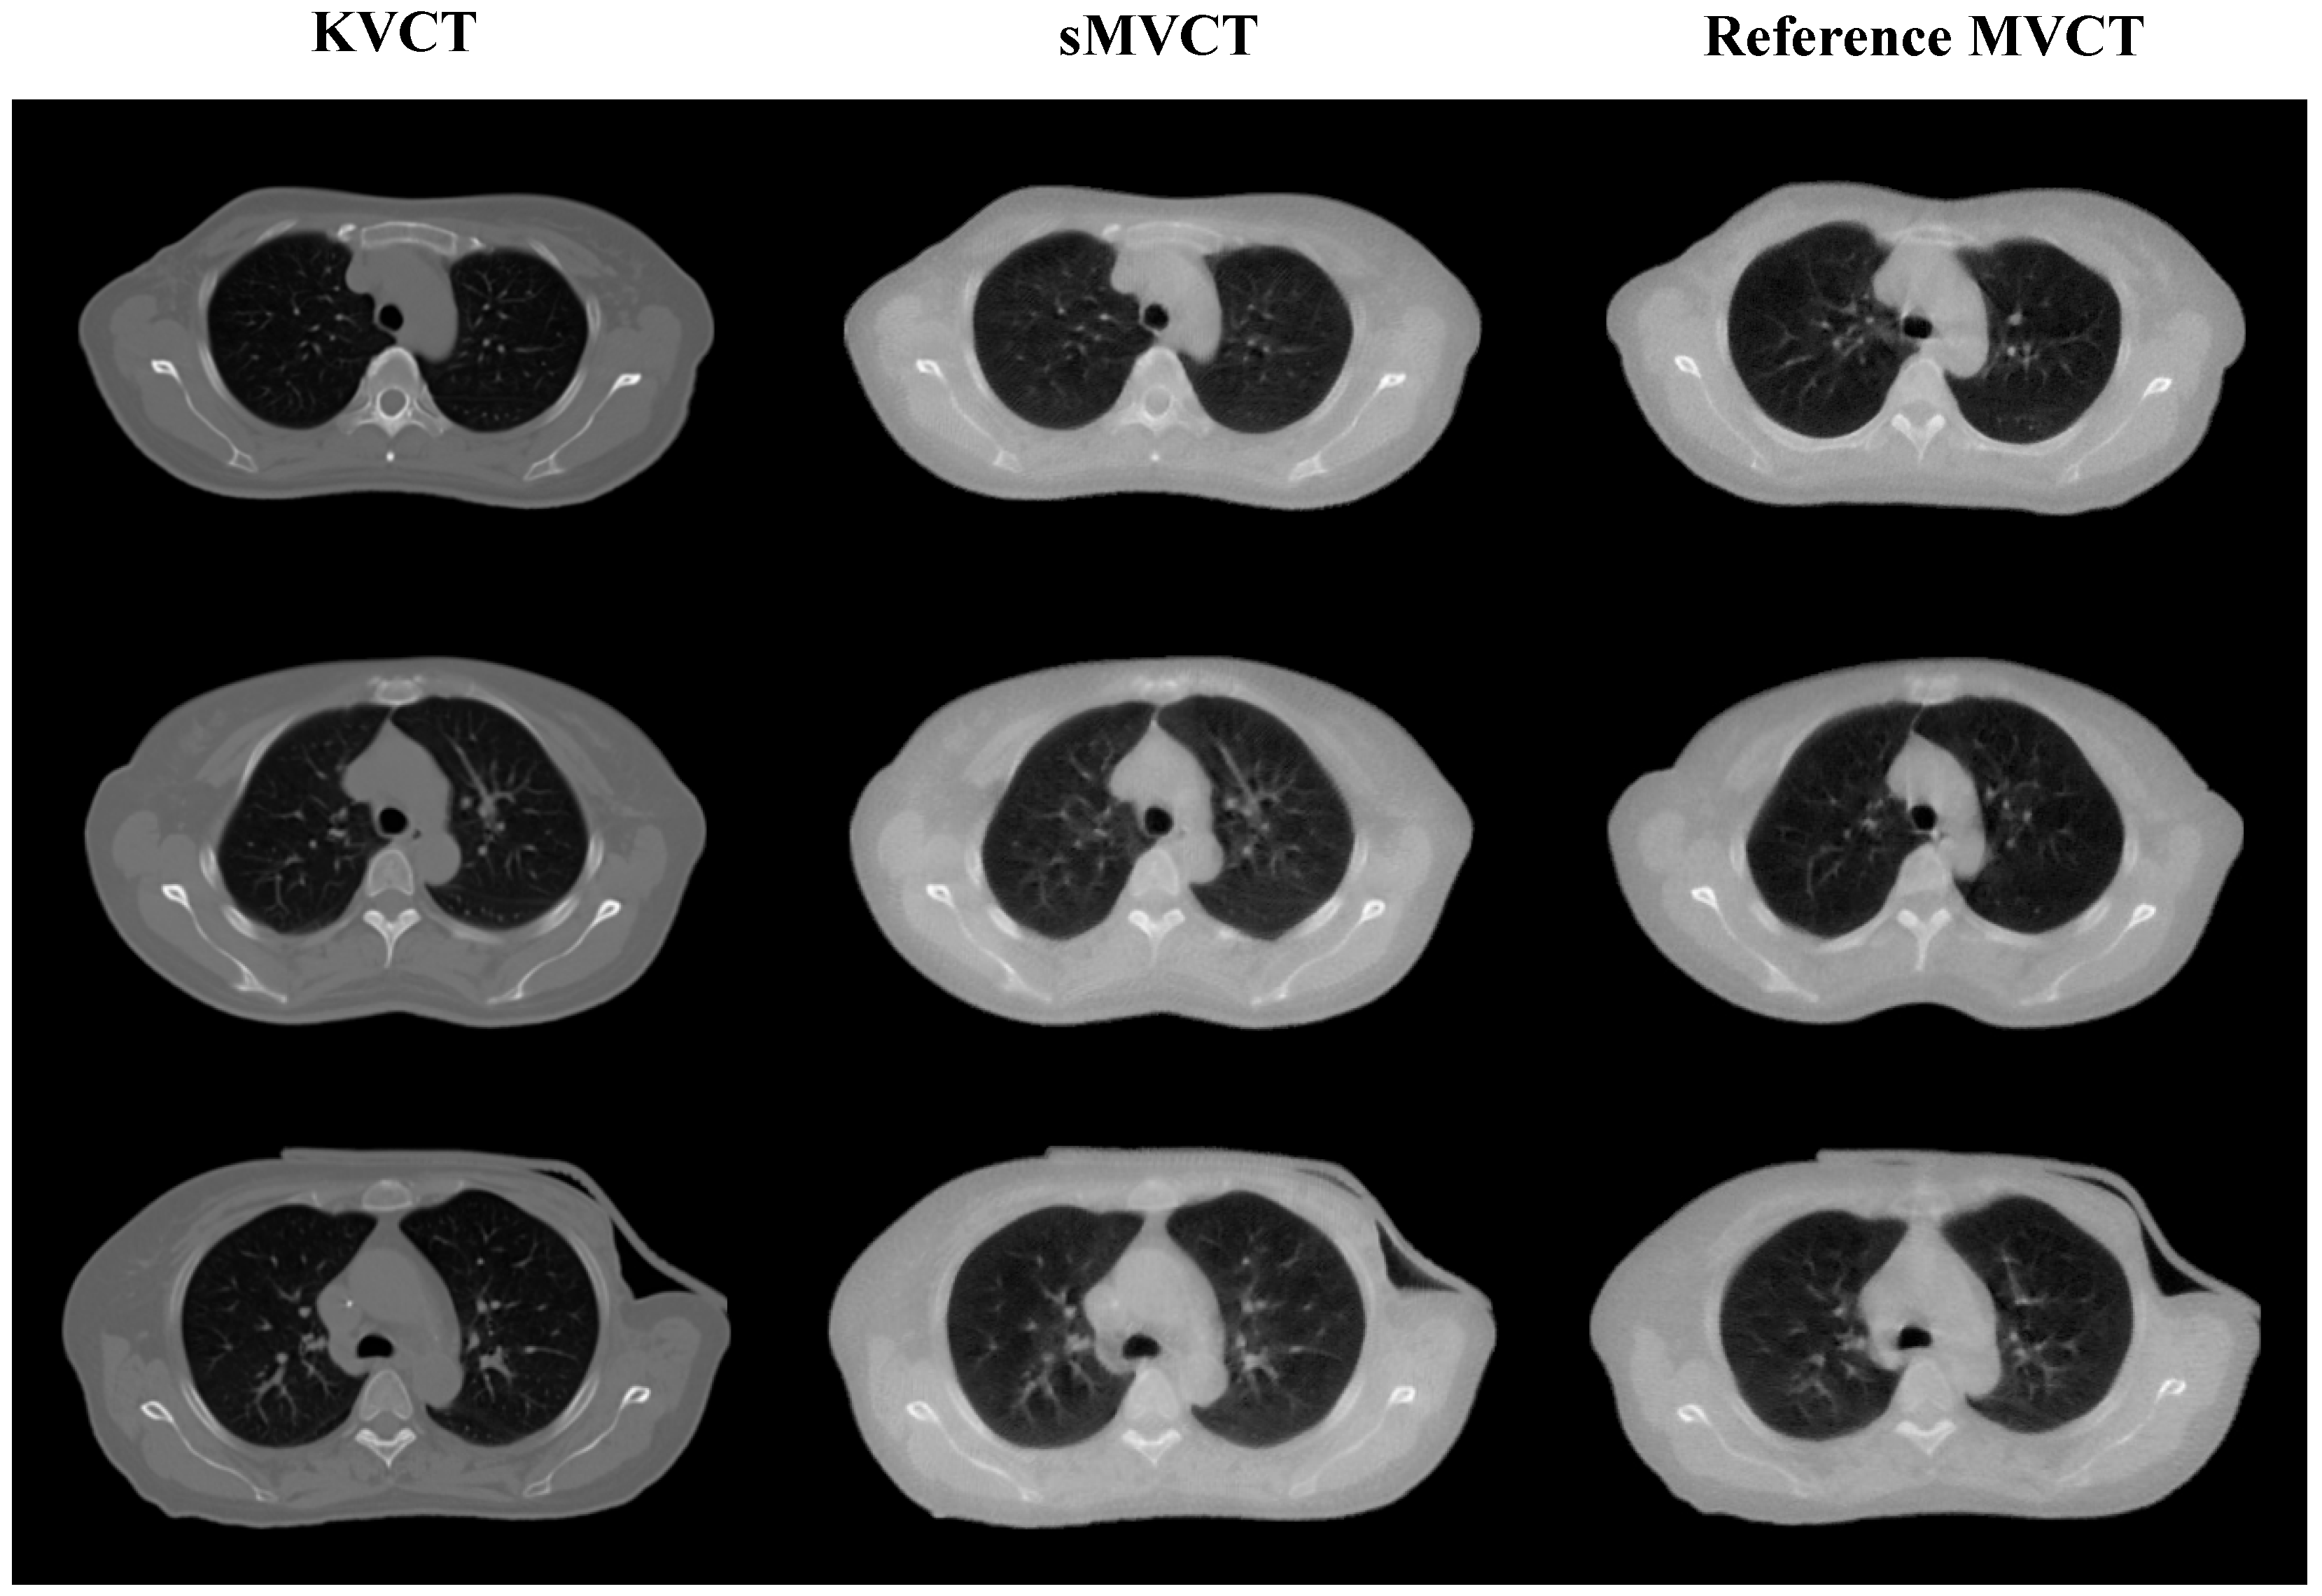

4.3. Results of Clinical Patient Data